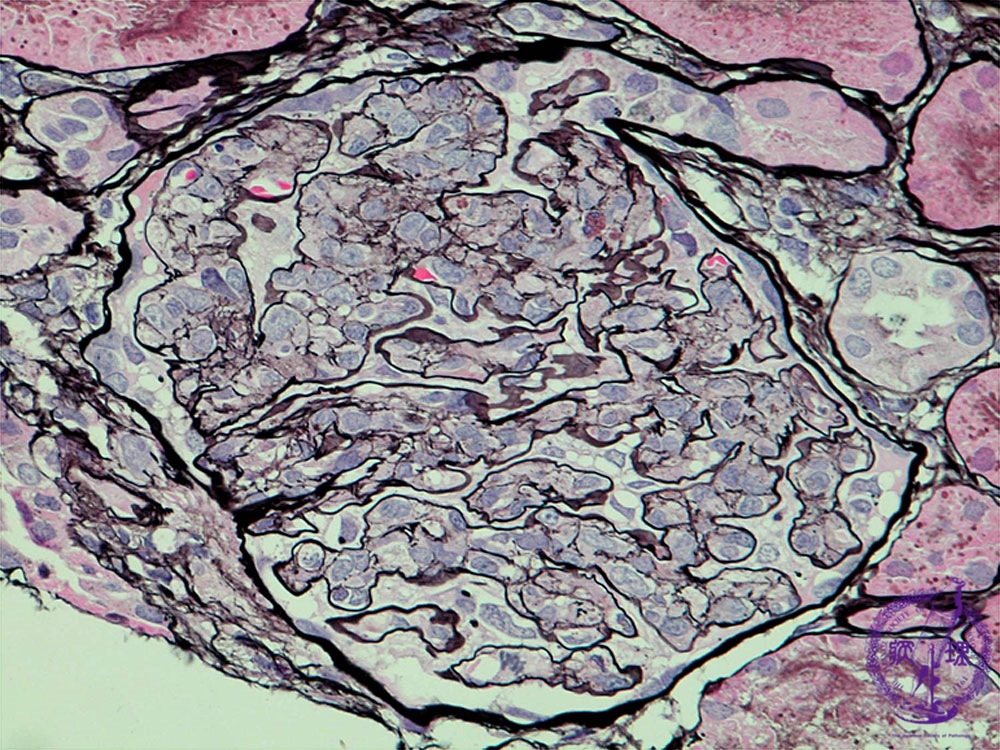

Microscopic findings (PAM, high power view): The glomerular capillary lumen narrows due to proliferation and accumulation of endothelial cells, neutrophils, macrophages, and mesangial cells.